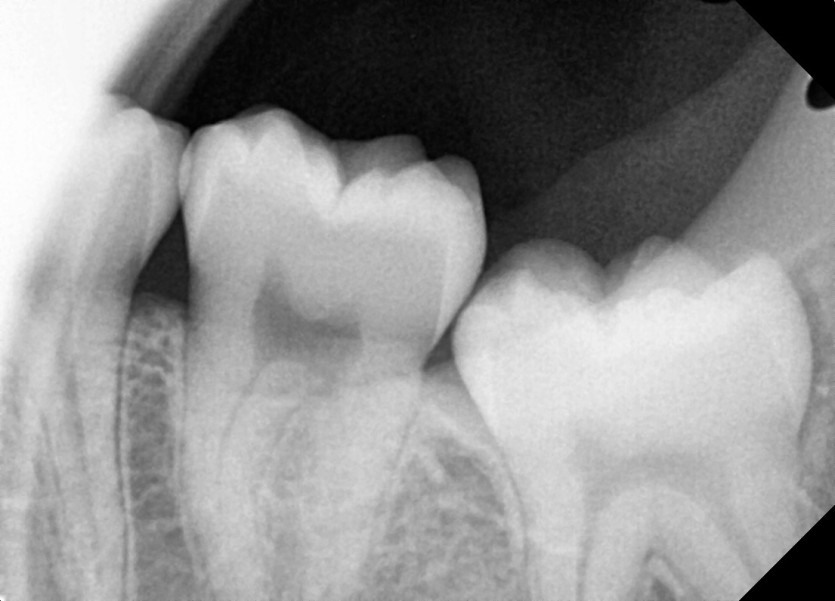

#28,38 사랑니 발치

구강 외과 전문의가 당일 발치했습니다.